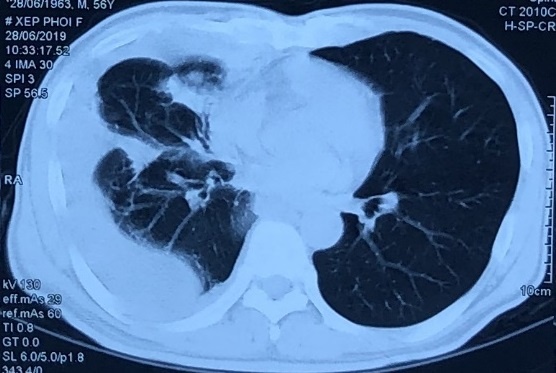

Hình ảnh chụp cắt lớp vi tính lồng ngực của bệnh nhân 56 tuổi. Ảnh: BVCC.

Bệnh nhân là Đ.V.T. (56 tuổi), tiền sử khỏe mạnh. Trước khi vào viện 2 tuần, ông T. ăn uống kém, sụt 2 kg, đau tức ngực phải, khó thở khi gắng sức, có ho khan. Nam bệnh nhân đi khám, chụp phim X-quang ngực có hình ảnh tràn dịch màng phổi phải, được nhập viện vào Trung tâm Y học hạt nhân và ung bướu, Bệnh viện Bạch Mai (Hà Nội).

Các bác sĩ đã tiến hành chọc hút dịch màng phổi xét nghiệm Cellblock (kỹ thuật khối tế bào). Kết quả cho thấy ông bị ung thư biểu mô tuyến phổi phải di căn hạch, màng phổi, xương đa ổ giai đoạn IV, đột biến gen EGFR trên exon 19.